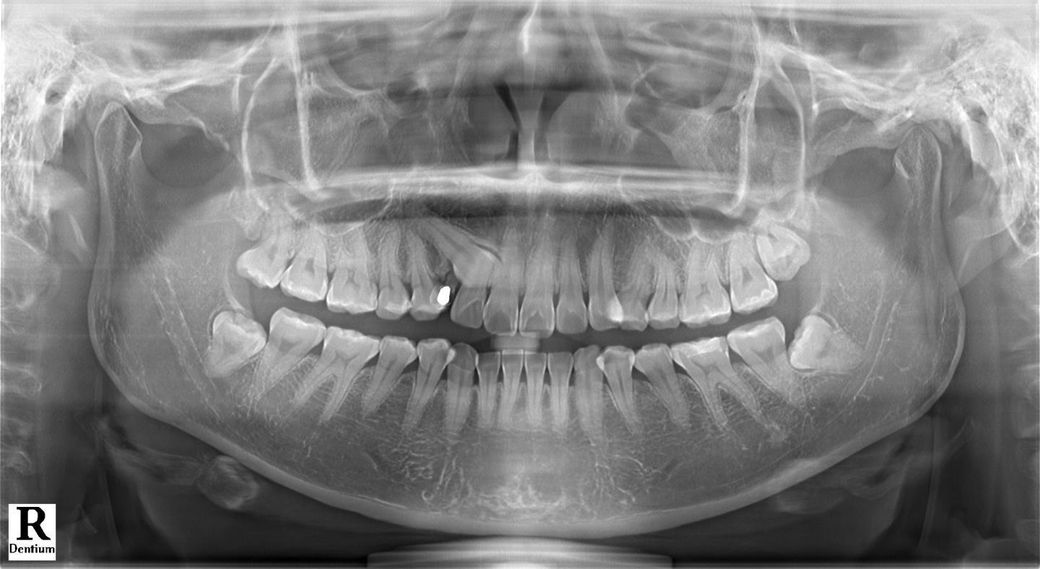

32살이라 교정을 통해 견인을해도 매복치가 잘 나올거라는 확신이 없다하셔서 발치쪽으로 생각중인데 다른 전문의 분들의 생각이 궁금해 질문 드립니다 유치는 발치를 꼭 하고싶은데 유치만빼고 매복치는 발치 안해도 괜찮을까요?

매복치를 그냥 둘지는 현재 매복치의 3차원적인 위치에 따라 다릅니다 다른 치아와 많이 겹쳐있으면 정상 치아의 뿌리를 녹이며 문제를 일으킬 가능성이 많습니다

이상태에서 매복 송곳니 그냥두며 정상적인 앞니 뿌리를 상하게 할 가능성 높습니다. 사진에서 겹쳐 보여 이미 앞니(측절치)가 손상되어 있을 가능성이 있습니다. 견인하지 않더라도 일단 매복치라도 뽑는 것을 추천합니다.